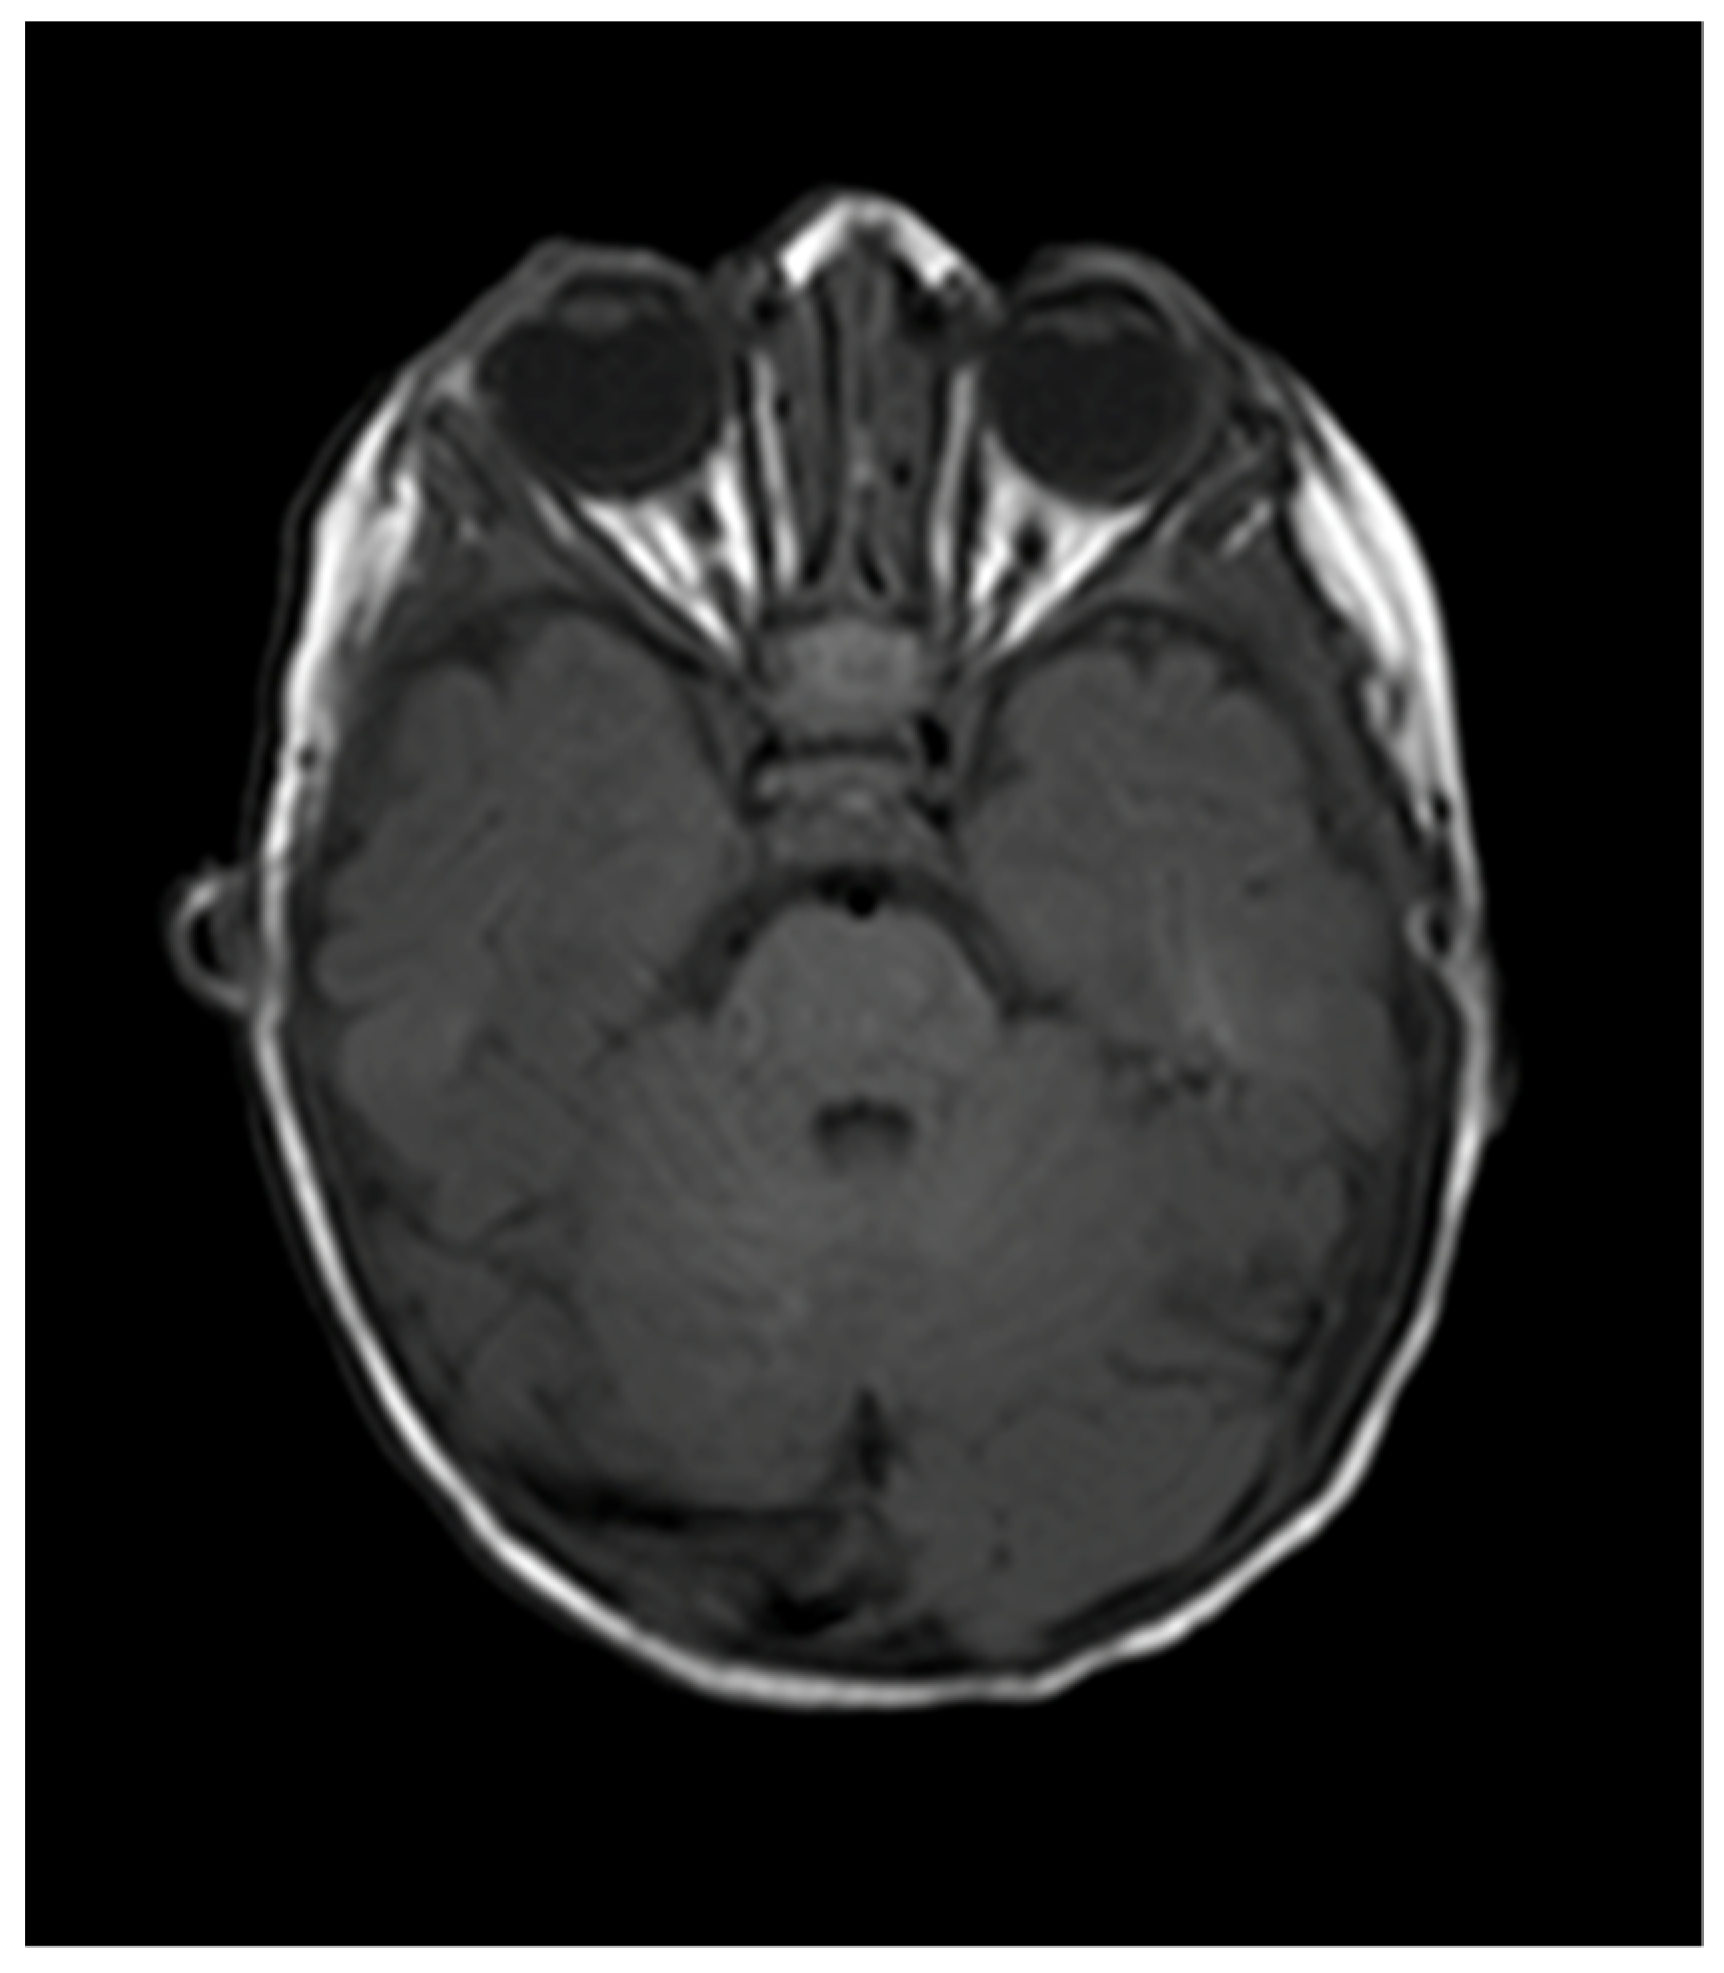

| Naughton et al., 2020 (this paper) | 6 weeks, female | Right CNVII palsy | Right orbit, right CPA and Meckel’s cave | Oral propranolol and topical timolol maleate 0.5% | Resolution |